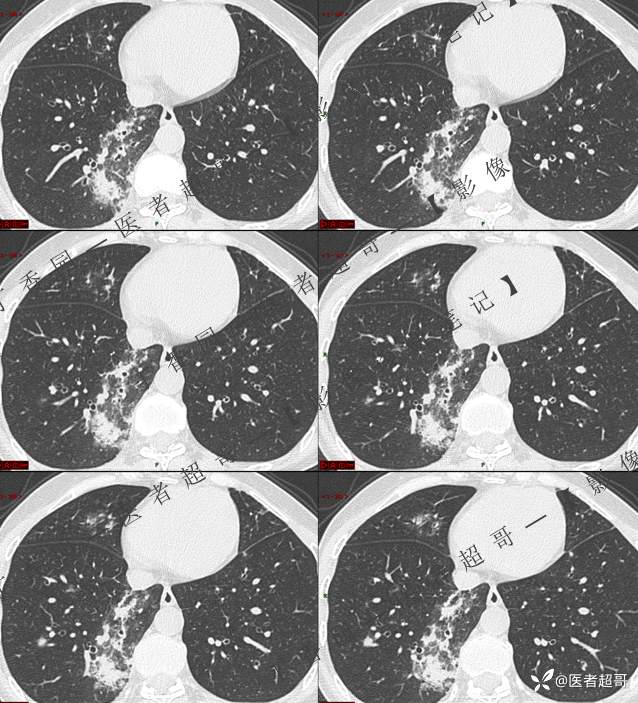

进一步做了相关实验室检查

第一次检查

第二次检查